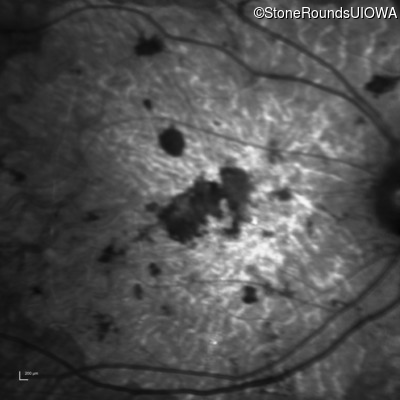

Infrared Fundus Photograph - Right - 20/150 sc

Exemplar

Infrared Fundus Photograph - Left - 20/300 sc